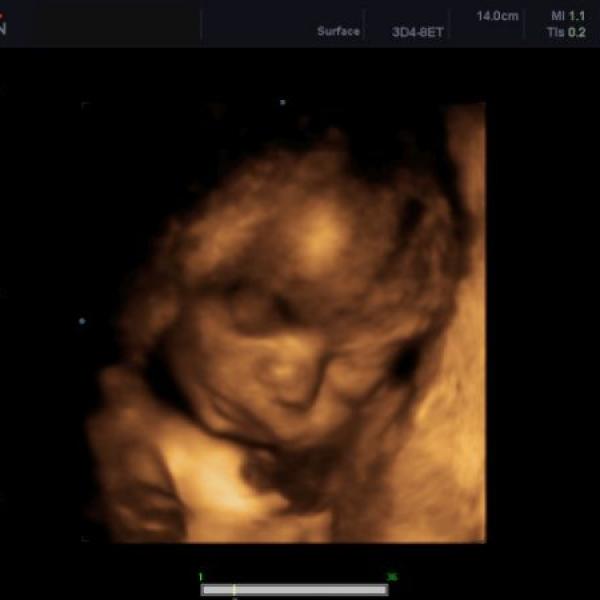

Ahojky spolutěhulky :) tak máme dneska za sebou 3D ultrazvuk - Kubík se vrtěl o sto šest, tak bylo těžký ho vyblejsknout - nakonec se z CDčka dá vybrat tak 5 fotek, jednu přikládám - má